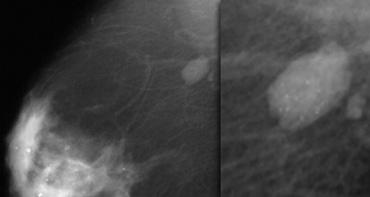

Đây là một khối bờ rõ không sờ thấy được kèm theo một nhóm vôi hóa chấm.

Khối được phân loại là BI-RADS 3.

Tiếp tục theo dõi bằng hình ảnh.

- Theo dõi ngắn hạn ban đầu đối với tổn thương BI-RADS 3 là nhũ ảnh một bên sau 6 tháng, sau đó khám theo dõi hai bên sau 12 tháng. Nếu ổn định, thực hiện theo dõi sau một năm và tùy chọn thêm một năm nữa.

- Nếu tổn thương không thay đổi trong quá trình theo dõi, đánh giá cuối cùng được chuyển thành BI-RADS 2 (lành tính) và không cần theo dõi thêm.

Theo dõi tại 6, 12 và 24 tháng không cho thấy thay đổi và đánh giá cuối cùng được chuyển thành Phân loại 2.

Tuy nhiên, bệnh nhân và bác sĩ lâm sàng vẫn muốn phẫu thuật cắt bỏ, vì bác sĩ X-quang không thể đưa ra chẩn đoán phân biệt rõ ràng.

Vì vậy, hãy thêm câu sau vào báo cáo của bạn:

- BI-RADS 2 (tổn thương lành tính).

- Thay vì ngừng theo dõi, chẩn đoán mô học sẽ được thực hiện theo nguyện vọng của bệnh nhân và bác sĩ lâm sàng.

Giải phẫu bệnh: Dị dạng mạch máu lành tính.